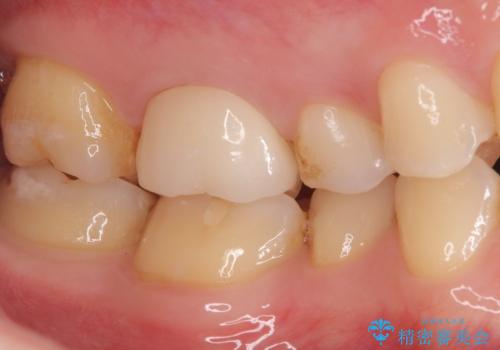

歯と歯の間の虫歯もセラミックで再発防止

- 左上6番の奥歯のコンタクト下カリエス(歯と歯の間の虫歯)を主訴にご来院されました。レントゲンと精密診査の結果、歯と歯の間という、再発しやすい部位の虫歯であることが判明。患者様のご希望と口腔内の状態を考慮し、虫歯を徹底的に除去し、精密で再発リスクの低いセラミッククラウンで修復する治療計画を立案しました。これにより、見た目の美しさだけでなく、長期的な歯の健康維持を目指します。

治療では、まず虫歯に侵された歯質を丁寧に除去し、セラミッククラウンを装着するための歯の形成を行いました。型取りから患者様の歯の形や色に合わせたオーダーメイドのセラミッククラウンを作製。セラミックは、隣接する歯との隙間なく精密に適合し、プラークが付着しにくいため、虫歯の再発を防ぐ効果があります。最終的に、精度の高いクラウンを装着し、咬み合わせを細かく調整しました。これにより、虫歯の再発を防ぎ、快適に食事ができる奥歯を取り戻していただけました。